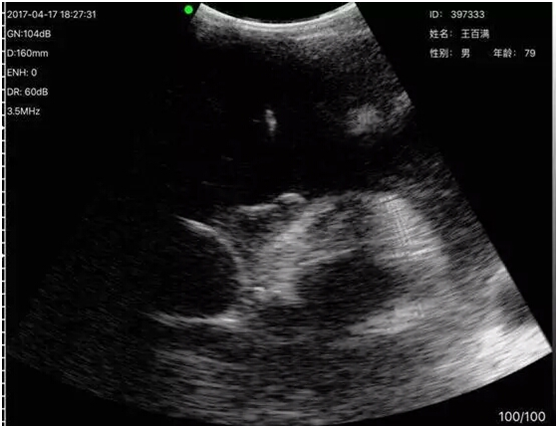

Ultrasound Dynamic Guidance Image Effect during Operation

Grandpa Wang had been Chronic Obstructive Pulmonary Disease for more than 30 years. Two months ago, his disease became worse for getting a cold, he had not received good treatment effect in the local hospital, came to The First People’s Hospital of Xianyang City through introduction and saw a doctor in the 2nd Endemic Area of Respiration Medicine. The medical permanence, Liang Jie recepted when he came here at the closing time. Mr. Liang found obvious symptoms including worse spirit, chess distress, pant, as well as much effusion in pericardium by CT-Scan Chest. Mr. Liang was aware of a bad thing and immediately reported it to the department’s director, Kang Kai. After director Kang came to the office, he used the wireless probe ultrasound on site to rapidly check Grandpa Wang, confirmed at once that there was much hydropericardium, and confirmed a better puncture position for Mr Wang. After communicating with Mr.Wang and his relation, Mr. Kang and Mr. Liang implemented the first hydropericardium puncture drainage real-time guided by the wireless probe ultrasounnd in real-time. Holding the ultrasound instrument, staring at the IPAD screen, Mr. Kang confirmed again the puncture position, direction, angle and depth during the operation, in the meanwhile, he directed Mr. Liang performed the puncture drainage with the aid of the ultrasound in real-time.Liquid in Mr. Wang’s pericardial cavity was slowly extracted by a thin hosepipe, his chest distress symptom gradually remitted and locked brows started to stretch, and the operation was successfully completed. Mr. Wang’s relation who was in anxiety outside the ward saw him perfectly calm, had become quite a different person between pretherapy and post-treatment, nearly believed their own eyes, and asked his feeling again and again. When Mr. Wang gave a positive answer, his relation held up their thumbs in excitement to the two doctors, and raised praises on the doctors with excellent medical skills and the advanced instrument.

Compared to four punctures of internal medicine(thoracocentesis, abdominocentesis, lumbar puncture and bone marrow puncture), Mr. Kang introduces that pericardiopuncture is more risk and difficult. In the past, patients with hydropericardium must left for the ultrasound department to position, and then the doctor could perform pericardiopuncture drainage, which course use static guidance. Now, with help of the wireless probe ultrasound, trained clinical doctors can perform real-time dynamic guidance operation with the ultrasound, which dispels misgivings about clinicians’inaccurate position, and which provides reliable guarantee for successfully implementing operation.